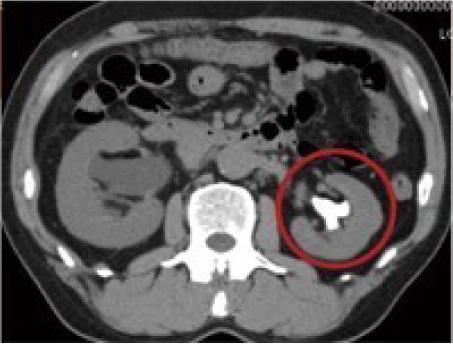

CT検査

尿路のどこに、どの程度の結石があり、それにより尿路がどのようになっているのか診る検査です。

※図:赤丸内の白く映っているのが結石-左腎結石